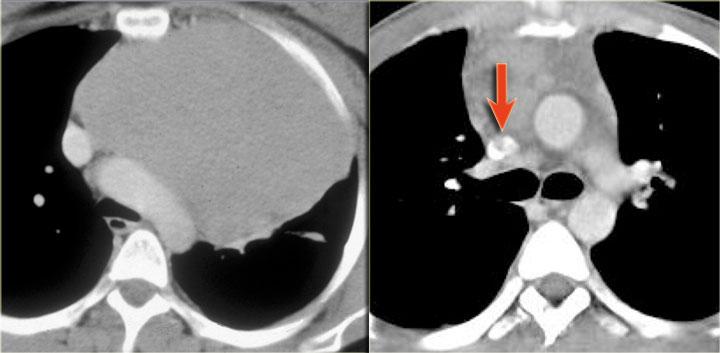

Phim ngực cho thấy các đặc điểm điển hình của u lympho Hodgkin, ví dụ: một khối trung thất trước.

Các hình ảnh CT của cùng bệnh nhân cho thấy một khối mô mềm lớn ở trung thất trước, xuất phát từ tuyến ức.

Có hạch cạnh khí quản kèm theo (mũi tên).

Hai trường hợp u lympho Hodgkin khác.

Các trường hợp này cũng cho thấy khối trung thất trước và hạch cạnh khí quản to.